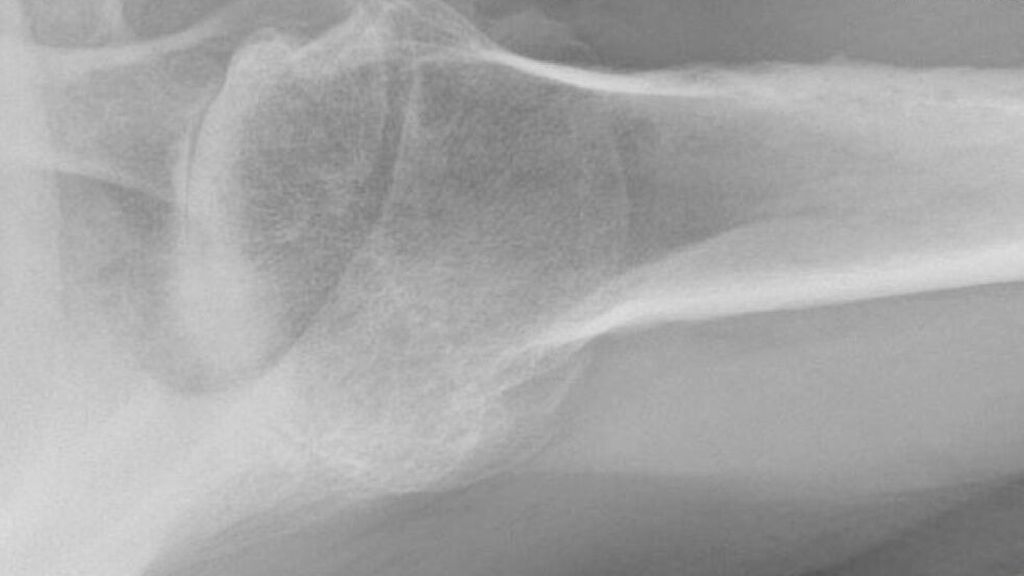

Inverse Schulterprothese (Abb. 2)

Neben den oben genannten gelenkserhaltenden Verfahren ist als gelenksersetzendes Verfahren die inverse Prothese Therapie der Wahl. Durch den ausgedehnten irreparablen Rotatorenmanschettendefekt kommt es durch die gestörte Biomechanik zu einer Dezentrierung des Humerus nach kranial und im weiteren Verlauf zu einer Defektarthropathie. Die Einteilung erfolgt nach der Klassifikation nach Hamada. Im Endstadium kommt es zu einer Acetabularisierung des Humerus mit dem Akromion und eine schmerzhafte Pseudoparalyse des Armes ist die Folge. Für diese Pathologie wurde von Grammont in den 1980er-Jahren die Deltaprothese entwickelt. Durch die Medialisierung und Kaudalisierung des Drehzentrums können mithilfe der inversen Prothese ein verbesserter Kraftvektor und eine bessere Vorspannung des M.deltoideus erreicht werden. Moderne Prothesensysteme und auch das bessere Verständnis der inversen Schulterendoprothetik haben in den letzten Jahren zu einer deutlichen Abnahme der Komplikationsrate und auch längeren Standzeiten geführt. Neben mechanischen prothesenbedingten Komplikationen kann es zu Akromionfrakturen, Luxationen, Infektionen und Funktionsseinschränkungen kommen. Auch die inverse Prothese kann bei Vorhandensein eines zusätzlichen Außenrotationsdefizites mit einem LD-Transfer kombiniert werden. Vorhandene Glenoiddefekte oder ausgedehnte Gelenksdeformitäten können ebenfalls mit einer inversen Prothese oder auch inversen Custom-made-Prothesen adressiert werden.